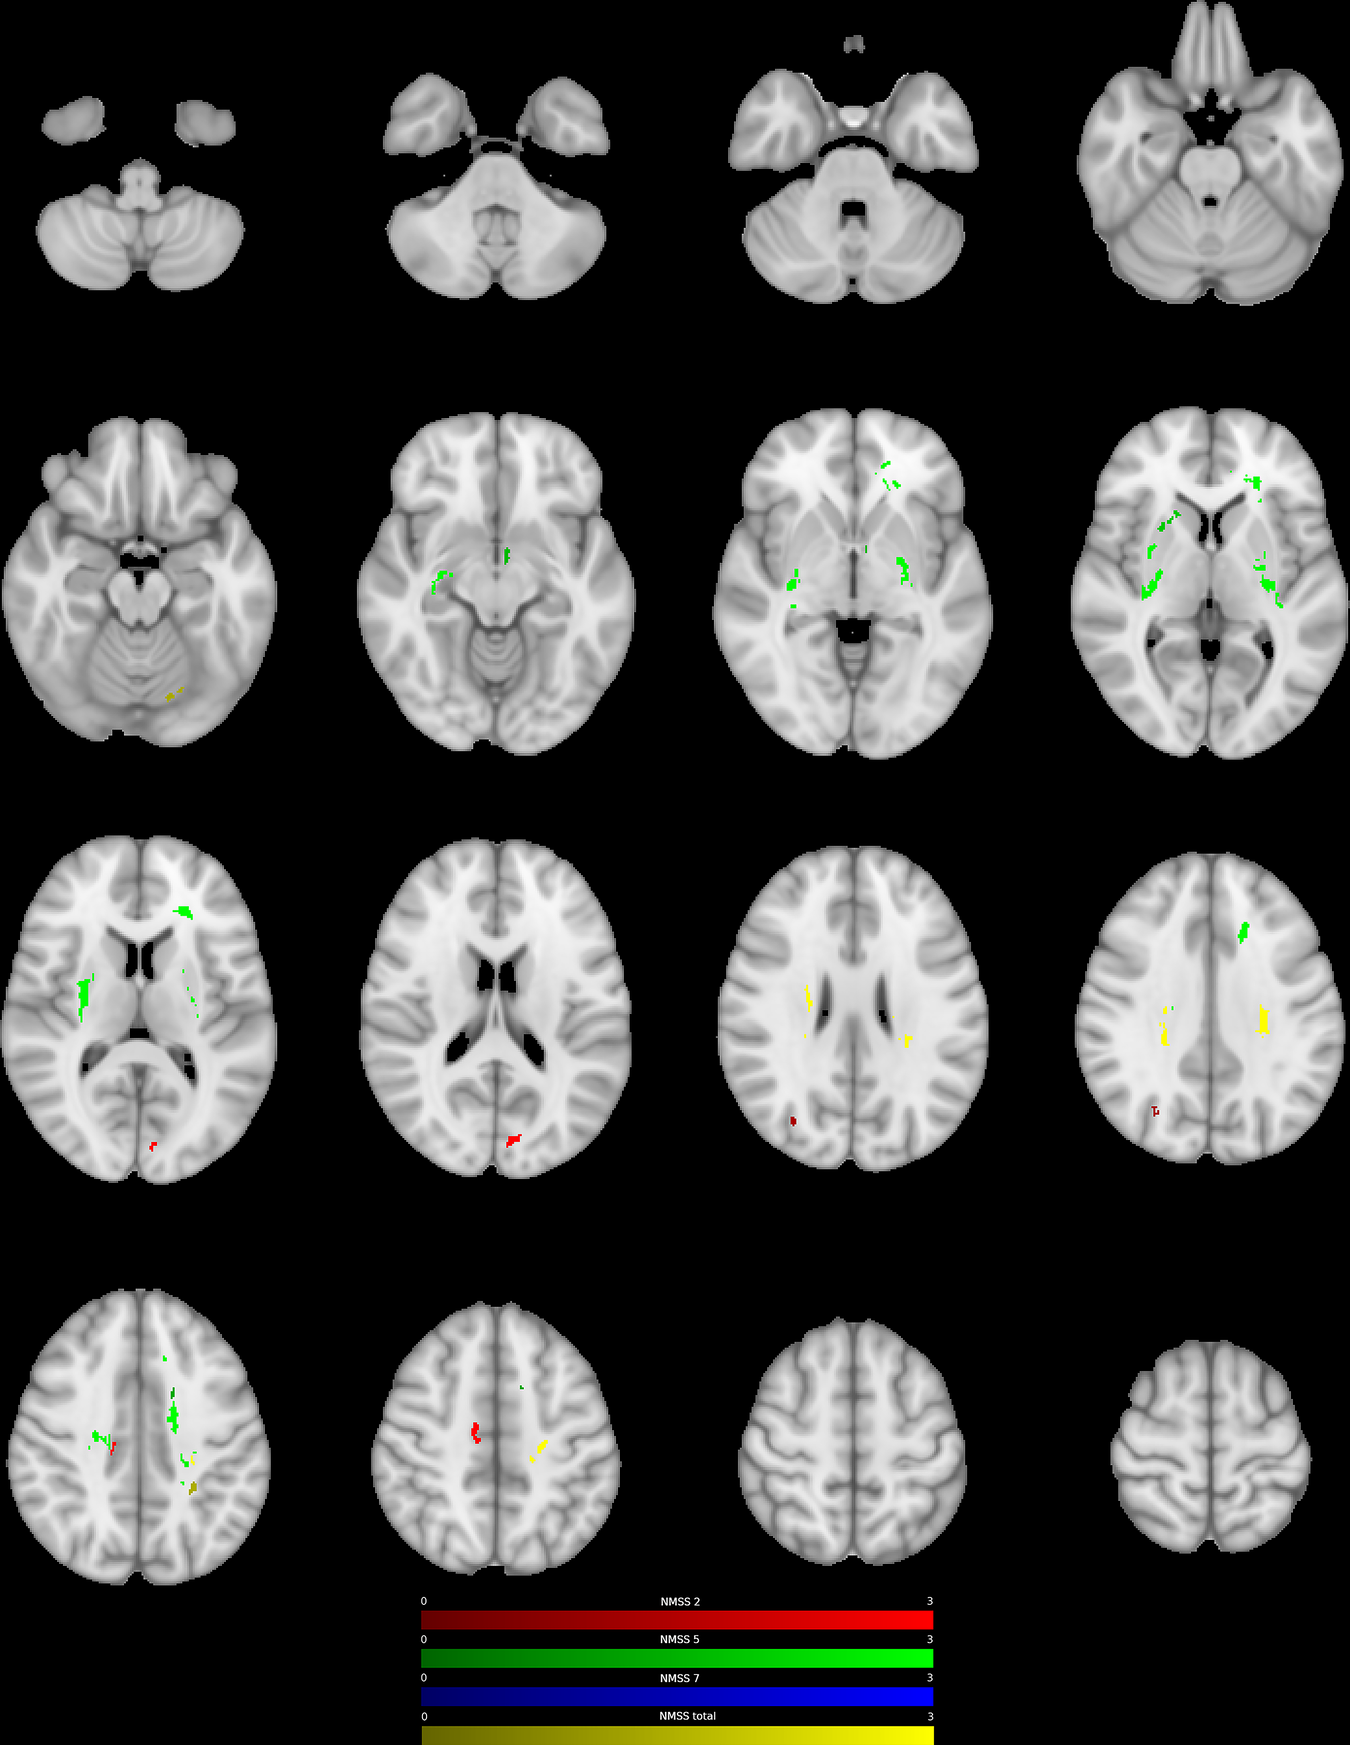

Fig. 2: Negative association between ODI and postoperative change in NMS.

Clusters with a negative association between PD patients’ ODI-values and postoperative change in NMSS-T (yellow), Domain 2 (sleep/fatigue, red), Domain 5 (attention/memory, green), and Domain 7 (urinary, blue), as revealed by the whole brain analysis. P values were corrected for multiple comparisons using a permutation-based approach.